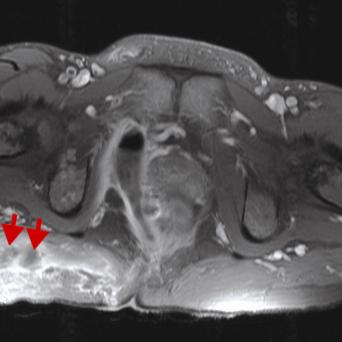

Lacertus fibrosus : à ne pas confondre avec le canal carpien !🎬

Le syndrome du lacertus fibrosus est une affection courante, mais encore largement méconnue. Souvent confondu avec le syndrome du canal carpien, son diagnostic est négligé ou posé tardivement, parfois après échec d’une chirurgie pour syndrome du canal carpien. Pourtant, certains signes sont caractéristiques et l’examen clinique permet de distinguer ces deux pathologies et d’orienter rapidement les patients. Flash interview du Dr Marc-Olivier Falcone, chirurgien orthopédiste et traumatologue, Paris.